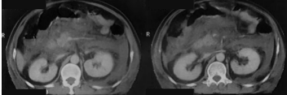

CT表现:平扫呈单发或多发圆形高密度影;肝内胆管结石:常为高密度,呈与肝内胆管走行一致的结节状影,常伴有周围胆道扩张;胆总管结石:多为高密度。结石上部胆管扩张。可见“环靶”征或“半月”征。

MRI表现:与结石成分有关:T2WI,高信号胆囊内可清楚显示低信号结石;胆管结石在T2WIMRCP上呈低信号,MRCP能显示梗阻上方胆管扩张程度,扩张胆管下端呈杯口状充盈缺损。